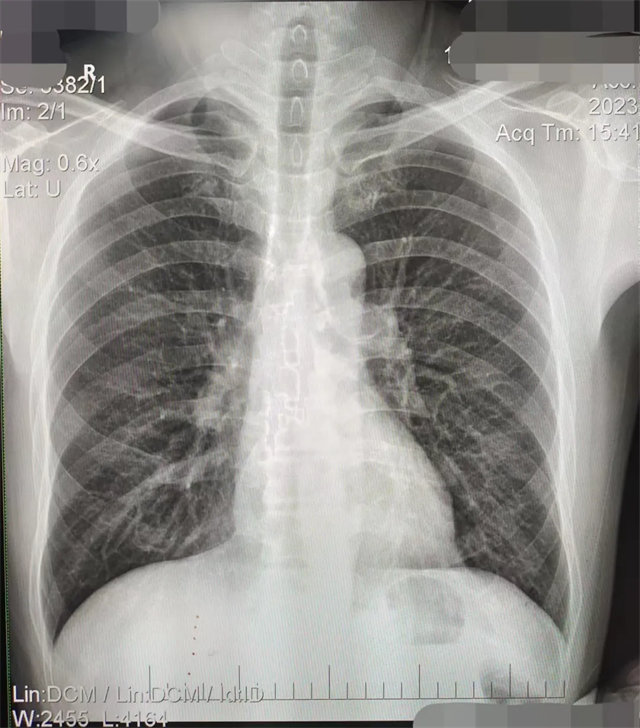

缺陷:左肩胛骨部分与左肺野重叠。

解决:使患者左肩旋前紧贴成像件重新曝光。